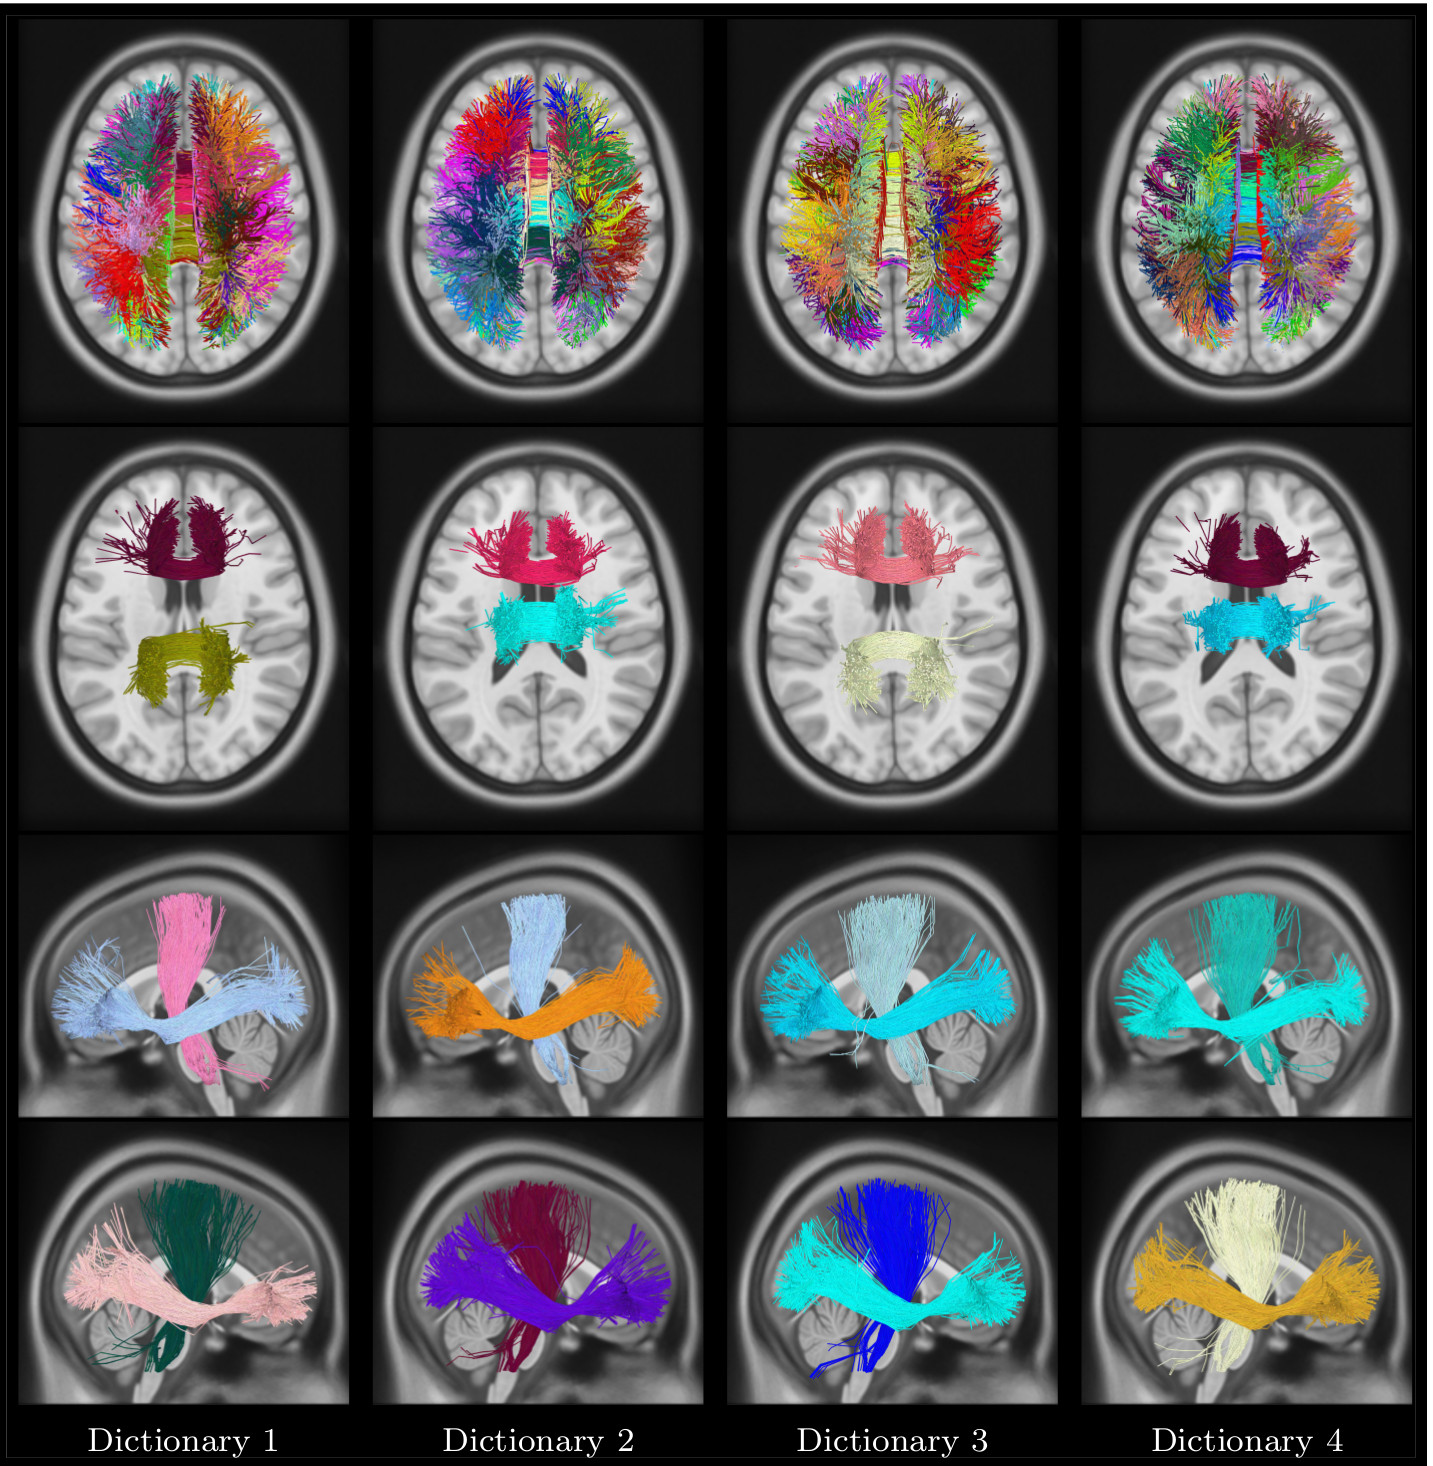

Refer to caption

Figure 9: Unsupervised multi-subject dictionary visualization. Four different dictionaries and corresponding bundles. Top row: Axial view of full dictionary with a unique color assigned to each bundle; Second row: Anterior Body, and Central Body bundles in Corpus Callosum; Third row: Left CST, and Left IOF bundles; Last row: Right CST, and Right IOF bundles. Each dictionary has a different color code, while the bundles respect that dictionary color-code. (m=50 bundles).

4.8 Application to automated tractography segmentation

In this section, we apply the proposed KSC method for the automated segmentation of new subject streamlines. Again, the focus of our analysis is on inter-subject variability and its effect on results. To label streamlines, we used as bundle atlas the dictionaries obtained from 40 unrelated HCP subjects (444 dictionaries, each one learned from 101010 subjects. Dictionaries were generated by sampling 500050005000 streamlines in each subject and employing MCP as distance measure. Note that expert-labeled streamlines could also be used as dictionary.

Figure 10: Automated segmentation visualization. Top row: full segmentation of 4 HCP subjects using dictionary D1, with a unique color assigned to each cluster, and same color code as D1. Rows 2-7: sparse code (bundle membership) visualization for the posterior body CC, anterior body CC, left IOF, left CST, right IOF, and right CST bundles. Membership values are represented by a color ranging from green (no membership) to red (highest membership).

The bundles encoded by these dictionaries are depicted in Figure 9. Moreover, segmentation results obtained for 4 different subjects using dictionary D1 are shown in Fig. 10. For each subject, we give the full segmentation as well as membership values for CC, left/right IOF, and left/right CST bundles. Additionally, to analyze the impact of sampling streamlines from a subject, segmentation results for 555 instances of subject 1 using D1 are provided in Supplement material. Once more, while we observe variability across segmented streamlines from different subjects, the results obtained by our method are globally consistent across subjects. Similar consistency is found across multiple instances of the subject 1 (see Supplement material, Fig. 5).